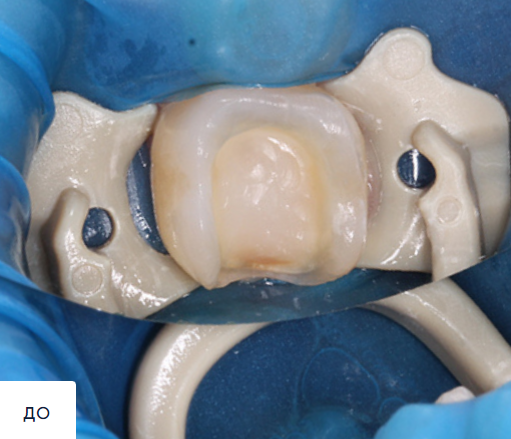

PRODENT CONCEPT (ПРОДЕНТ КОНЦЕПТ): работы специалистов (13)